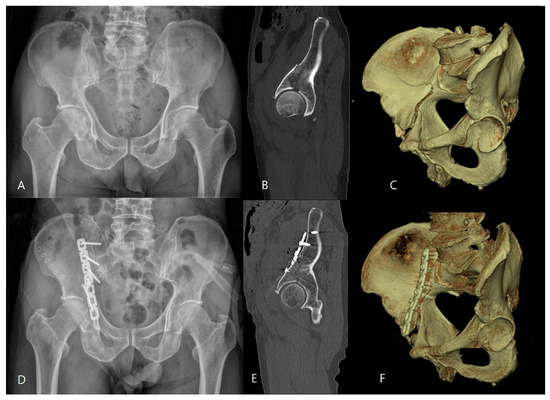

Compression Osteosynthesis Without Iliac Crest Osteotomy Through the Anterior Iliac Approach for Incomplete High Anterior Column Fractures of the Acetabulum: A Case Series and Surgical Technique

by Young-Ho Cho, Young-Soo Byun and Seong-Eun Byun

J. Clin. Med. 2026, 15(7), 2739; https://doi.org/10.3390/jcm15072739 - 4 Apr 2026

Introduction: An incomplete high anterior column fracture of the acetabulum is commonly considered to require completion of the fracture. However, reduction may become more difficult after completing the incomplete fracture due to plastic deformation. This study describes a surgical technique of compression osteosynthesis [...] Read more.

Introduction: An incomplete high anterior column fracture of the acetabulum is commonly considered to require completion of the fracture. However, reduction may become more difficult after completing the incomplete fracture due to plastic deformation. This study describes a surgical technique of compression osteosynthesis without completing the incomplete fracture and evaluates the clinical and radiographic outcomes. Materials and Methods: In this retrospective study, 25 patients with incomplete high anterior column fractures met the inclusion criteria. The fracture was reduced and stabilized by compression osteosynthesis through the anterior iliac approach without completing the incomplete fracture in the iliac wing. Patient demographics, the mechanism of injury, associated injuries, time to surgical reconstruction, operation time, and postoperative complications were analyzed. The quality of reduction and outcome were evaluated according to Matta’s criteria. Results: The mean operation time was 110 ± 23 min (range, 75–160). All fractures achieved bone union at a mean of 10.2 ± 1.4 weeks (range, 8–14). The quality of fracture reduction was graded as anatomical in 22 hips, imperfect in one and poor in two. Clinical results were excellent in 19 patients and good in six, and radiographic results were excellent in 22 patients and good in three. No statistically significant differences were observed between patients with and without quadrilateral plate fractures. Lateral femoral cutaneous nerve injury occurred in 13 patients (52%), mostly without significant symptoms. One patient experienced vascular injury. Conclusions: Incomplete high anterior column fractures can be effectively reduced and stabilized by compression osteosynthesis through the anterior iliac approach without completing the incomplete fracture in the iliac wing. This case series demonstrated favorable clinical and radiographic outcomes using this surgical technique. However, because this study was a retrospective case series with a small sample size and no comparative control group, further studies are required to confirm these findings. Full article